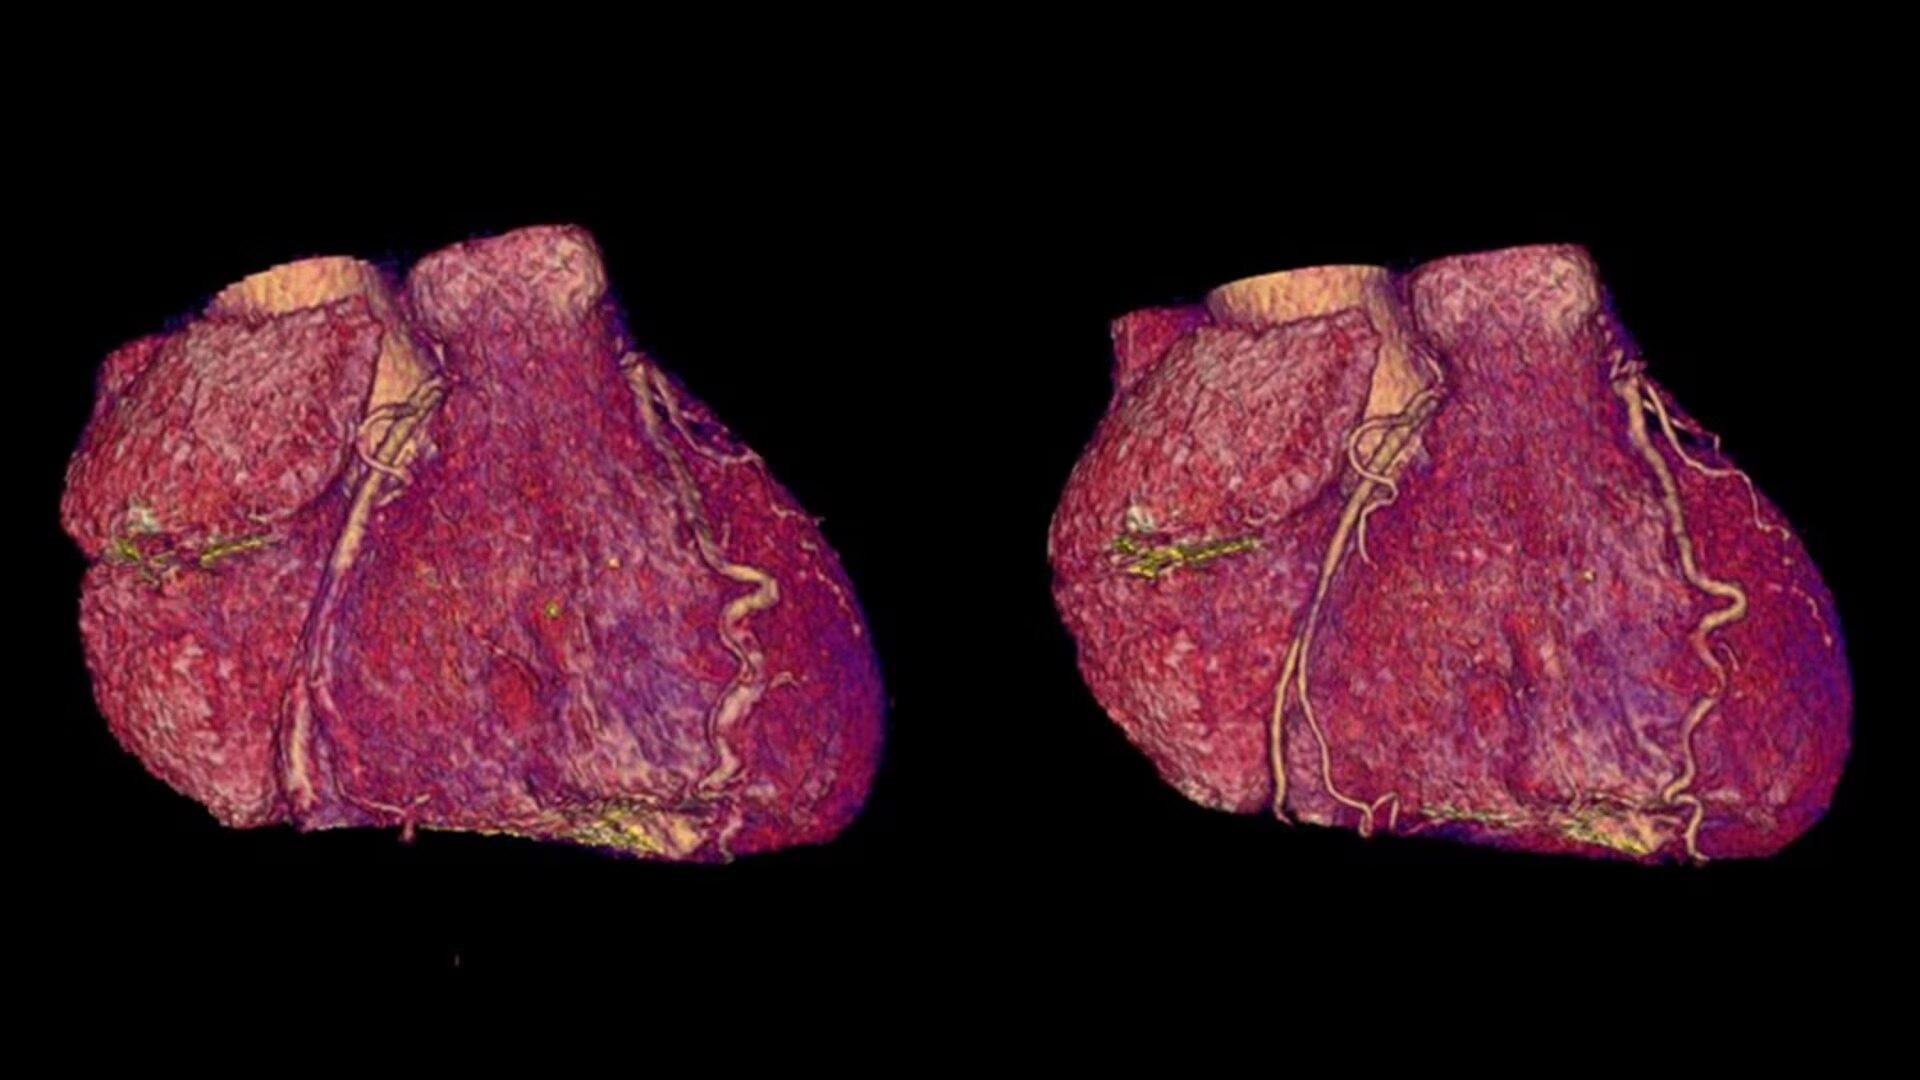

SnapShot Freeze 2

Intelligent and automated whole-heart motion correction for enhanced Cardiac CT imaging.

Motion correction

6x reduction in motion artifacts1

Temporal resolution

19.5 msec effective temporal resolution at 0.23s/rotation gantry speed2

Automated

Whole-heart motion correction